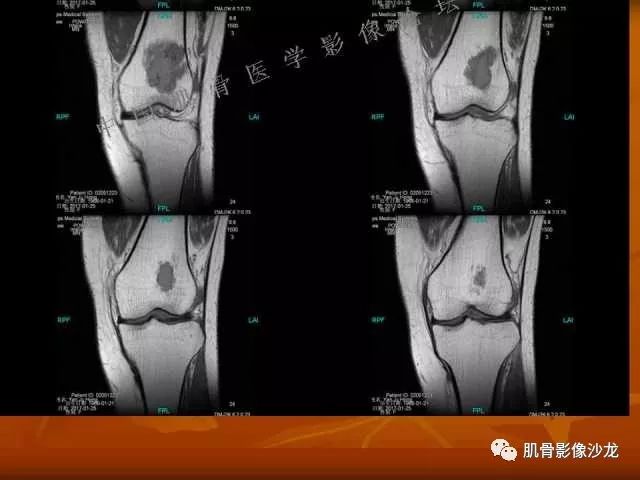

西门吹雪 :股骨下段,偏侧破坏,长T1混杂T2,移行带较窄,但局部边缘欠规则。周围骨髓水肿不明显,软组织结构清晰,T2病变上部片状低信号 , 膨胀不明显。

阳光明媚 :股骨远端前部可见片状长T1、长T2不均信号影,压脂序列呈不均高信号影,平片无明显钙化,边界清。内有纤维、粘液,

雪舞 : 股骨下端,皮质下偏心性溶骨性破坏,分叶状,T2混杂高信号。无明显软组织肿块。X片未见异常。

阳光明媚:骨皮质还是比较完整的

飞鹰行动 : 第一列可以看见T2小结节样高信号,周围有纤维组织环绕

高回青 : 另外还可以见到扇贝状分叶

2、软骨基质T2WI高信号,软骨小叶分叶状,也就会出现高老师提到的骨内膜扇贝形压迹。一般认为骨内膜扇贝形压迹超过骨皮质厚度的2/3是软骨肉瘤在长管状骨的特征性表现。如上图。3、软组织肿块或肿胀;